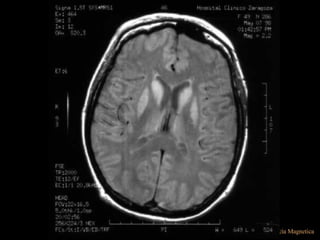

ENF DESMIELINIZANTES

SE VE LA ISQUEMIA

EN SUST. BLANCA

ALEJANDRA GALVEZ

FLAIR

EL AGUA

DIO SEÑAL?

¿COMO SE VE

LA SUST. GRIS?

COMPARADO

CON UN T1

LA SUST. BLANCA?